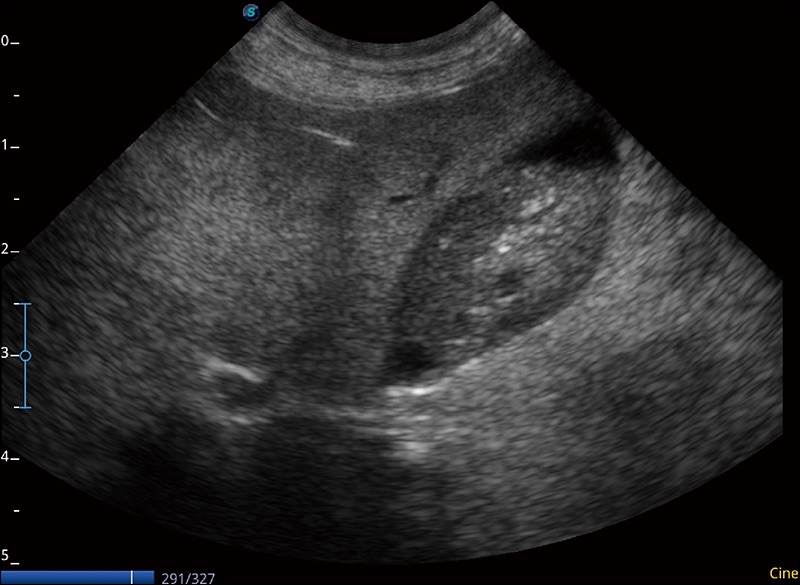

扩展成像

支持线阵和凸阵探头,一键操作即可获得更宽的图像视野

实时宽景成像

可实时观察感兴趣区域和病变位置